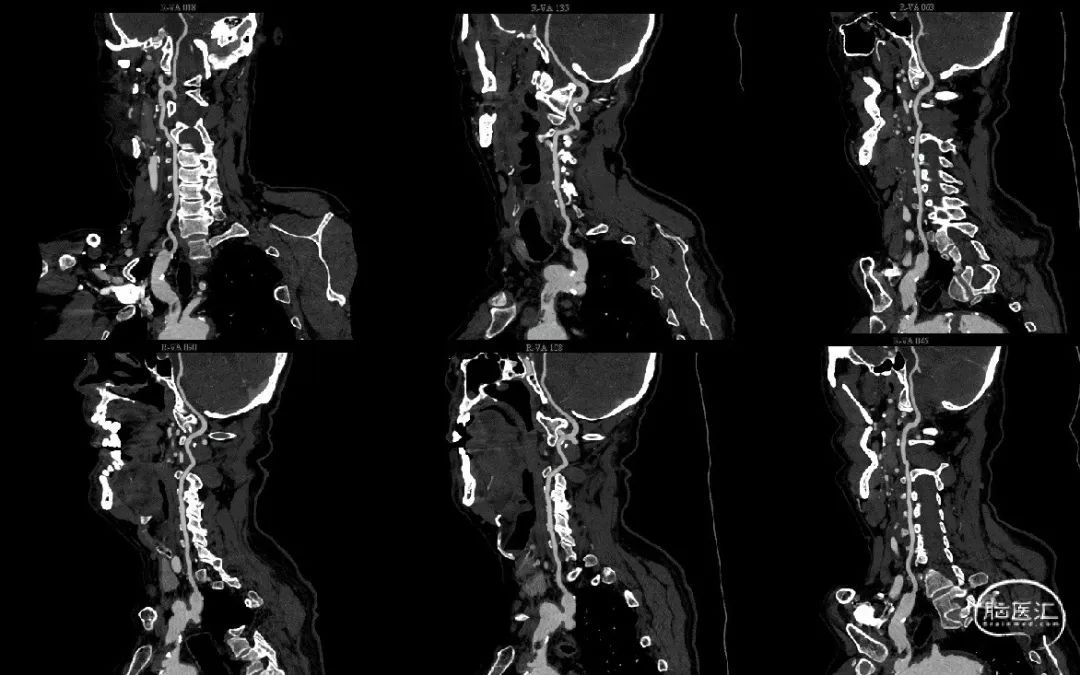

继续筛查颅外段血管完善颈部血管CTA:可见头臂干钙化斑块,伴低密度影,考虑附壁血栓。

复查颈部血管CTA提示血栓较前明显减小。

抗凝一周后复查颈部血管CTA,血栓明显减小,血栓附着于头臂干左前侧壁。

此时患者的头臂干血栓应属于漂浮血栓(free floating thrombus, FFT), 即一端附着于动脉壁,一端游离于血管腔内,此类型血栓会随收缩压、舒张压交替至血栓来回摆动,脱落风险较高。

附壁血栓可见链接蒂结构,附壁血栓逐渐溶解,链接蒂结构也可见消解,如继续溶解可能出现链接蒂断裂,导致远端血栓脱落至远端栓塞。